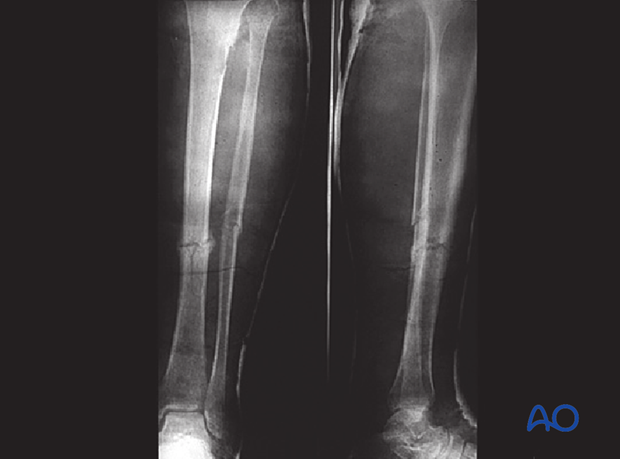

These x-rays show a simple transverse diaphyseal fracture of the tibia with an associated simple oblique fracture of the fibula. The treatment plan for this fracture is nonoperative.